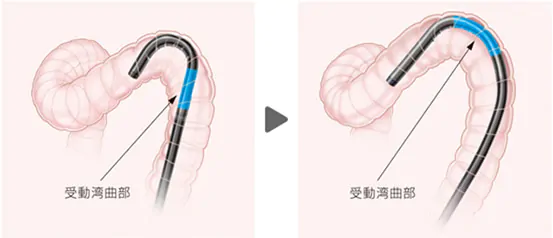

受動湾曲

内視鏡スコープが大腸の壁に当たると自然に曲がっていく設計により、屈曲部もスムーズに通過するようになりました。それにより盲腸への速やかな到達と、患者様の苦痛軽減に貢献いたします。